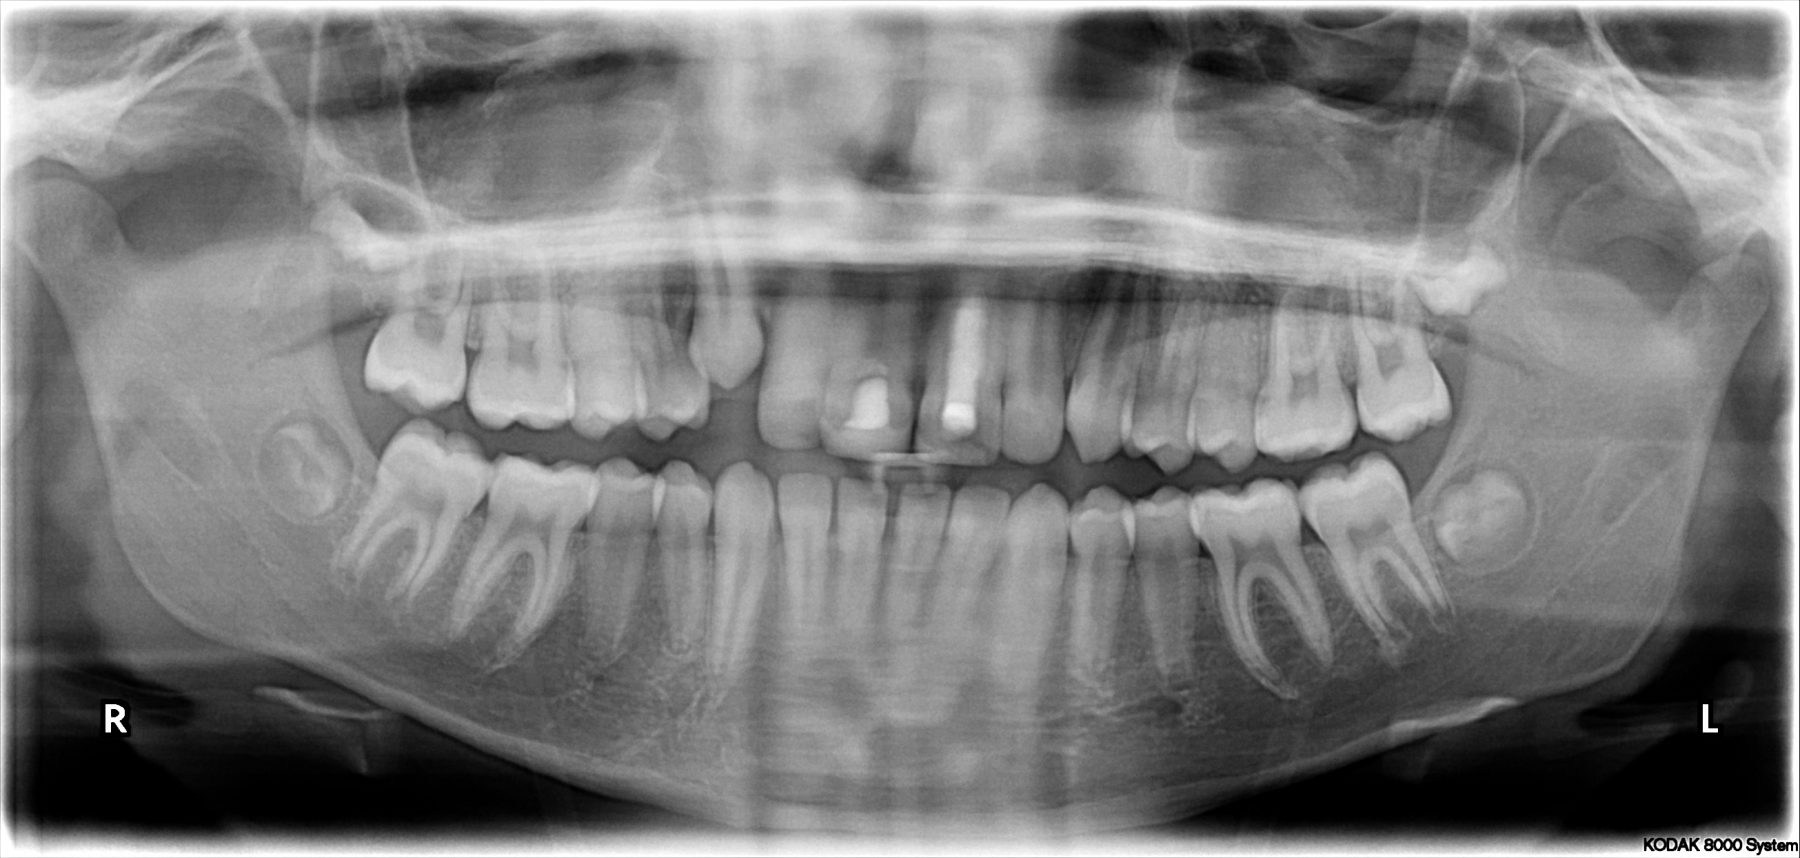

Als we denken dat een autotransplantatie een goede optie voor een patiënt is, worden eerst lichtfoto’s, röntgenfoto’s en gebitsafdrukken gemaakt en wordt een plan gemaakt in een speciaal team, het autotransplantatieteam.

De MKA-chirurg (kaakchirurg) dr. Aarnoud Hoekema werkt op de afdeling Mond-, Kaak- & Aangezichtschirurgie van Frisius MC Heerenveen (voorheen Tjongerschans ziekenhuis). Hij bespreekt vooraf de opties, de procedure, de risico’s en maakt een digitale scan van het te transplanteren gebitselement, om te zien of transplantatie een geschikte behandeloptie is.

Dan print hij het te transplanteren gebitselement uit in kunststof op 115% van de werkelijke grootte, als pas-malletje. Hiermee kan tijdens de operatie eerst gepast worden of de plek waar het kiesje heen getransplanteerd wordt wel de goede vorm heeft.

Pas als dat zo is, wordt het te transplanteren kiesje daadwerkelijk uit de kaak geopereerd en direct in het inmiddels pasklare gat geplaatst. Hierdoor is het trauma op het transplantaat zo klein mogelijk en de overlevingskans zo groot mogelijk.